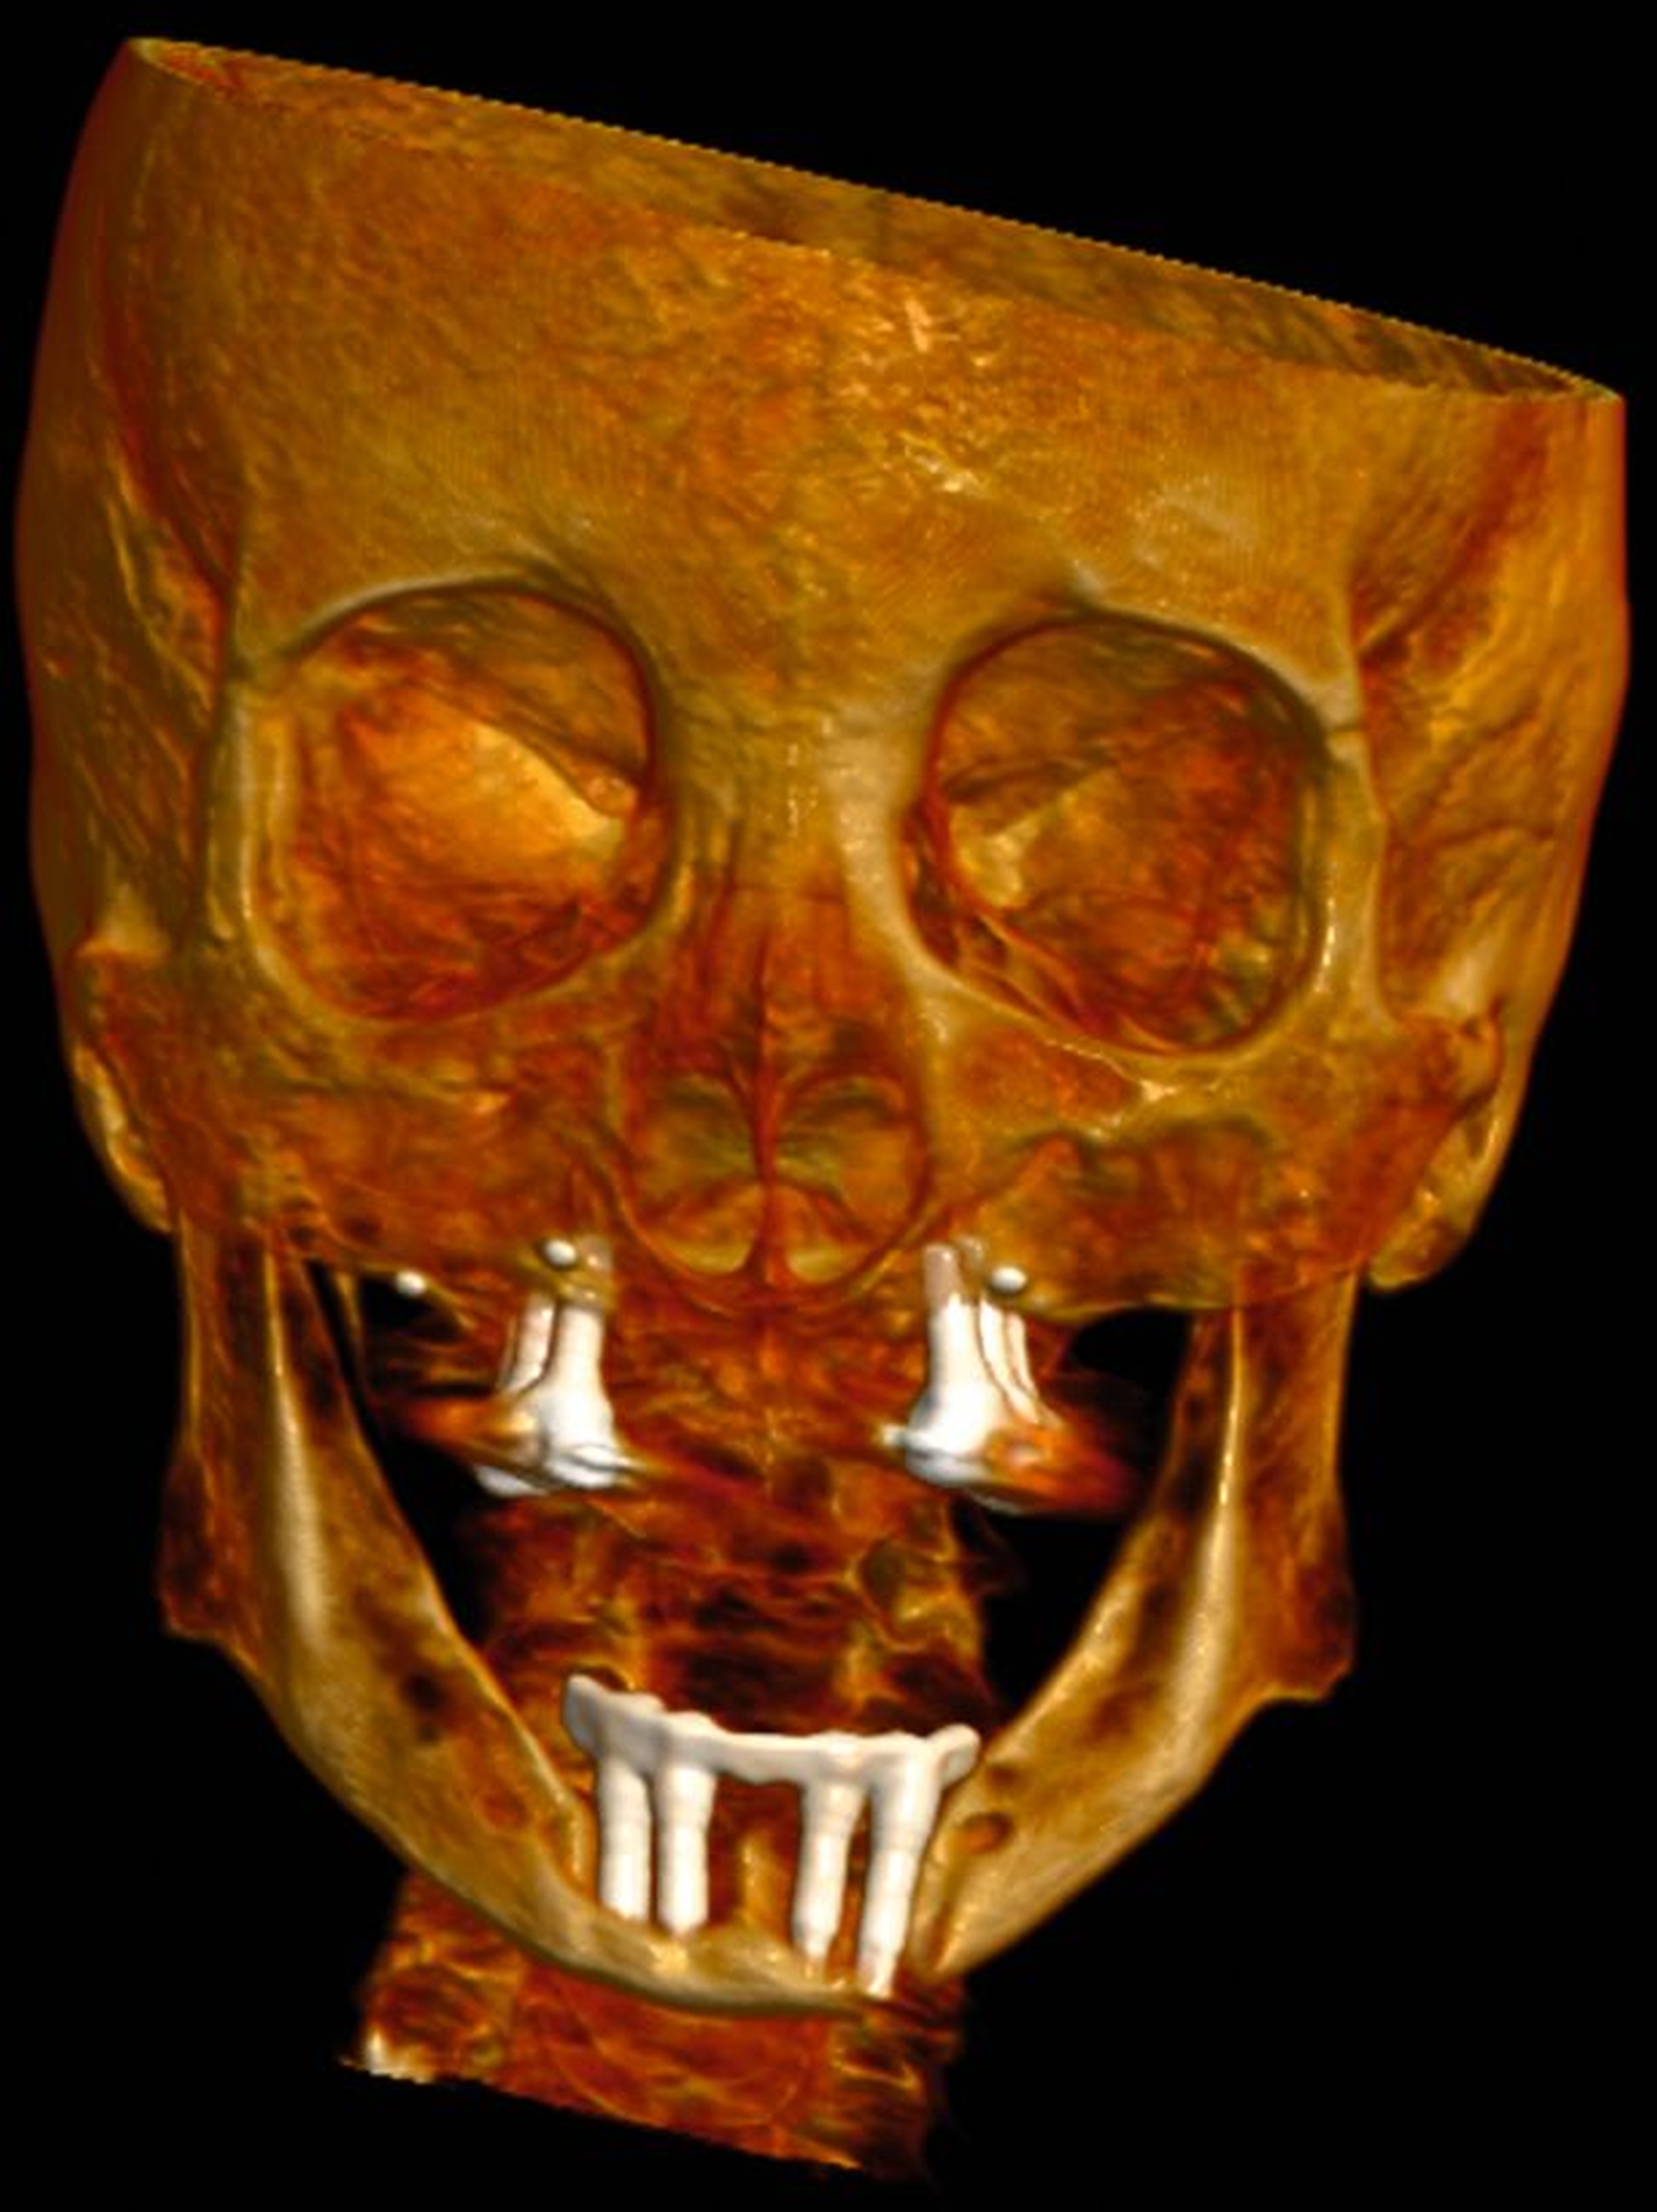

In der Panoramaschichtaufnahme zeigten sich an allen Implantaten ausgeprägte Knocheneinbrüche. Die Implantate in regio 33 und 32 waren vollständig von Osteolysesäumen umgeben, distal des Implantats in regio 33 stellte sich eine knöcherne Unterbrechung des Unterkiefers dar. Die anschließend angefertigte CT-Bildgebung des Unterkiefers und der Nasennebenhöhlen zeigte ausgeprägte osteolytische Säume um alle Implantate im Ober- und Unterkiefer mit einer knöchernen Unterbrechung des corpus mandibulae in regio 33. Weiterhin kamen weichgewebedichte Verschattungen beider Kieferhöhlen (links vollständig, rechts basal) und des sinus frontalis et ethmoidalis links, die mit einer chronischen Sinusitis vereinbar waren, zur Darstellung.